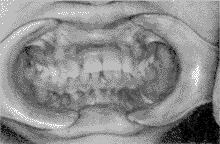

典型病例: 王某某,女,15 岁,检查:上下第二磨牙均已萌出建立咬合,左右第一磨牙为中性关系,上下牙列基本整齐,上切牙唇倾,有散在间隙,下前牙咬及上前牙舌侧牙龈,切牙覆盖9 mm,下牙弓spee 曲线陡峭,开唇露齿,面下1/3 过低,下颌角低平。矫治过程:第一、二磨牙粘固带环,其它牙齿贴方丝弓托槽,直径0.41 mm镍钛圆丝启动,戴前牙平导板(后牙离开4 mm),逐步更换0.46 mm镍钛圆丝及0.41 mm×0.56 mm,0.46 mm×0.63 mm 镍钛方丝整平牙弓,并开始进行后牙颌间“W”形牵引,6 个月后前牙覆

正常,开始内收上切牙,进行咬合调整,15 个月后完成矫治(见图2)。矫治前后头影测量结果见表2。

矫治前 矫治后

图2 深覆

矫治前后咬合正位像